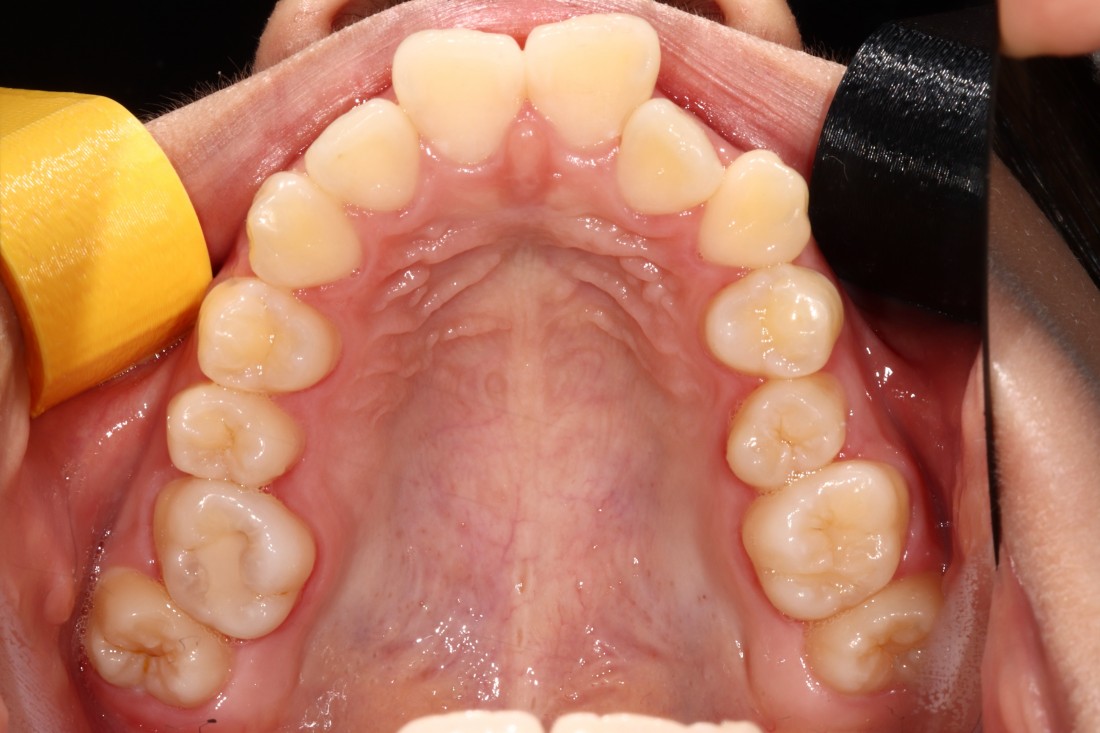

광주 성인 교정치과에서

충치치료와 교정진료를 동시에 받으신

성인 여성 환자분의 케이스입니다.

충치치료 전에는 은색 보철물이 있던 자리에

교정진료의 마무리와 동시에

치아색 보철물을 씌워서

치아교정 + 충치치료를 동시에 진행하였습니다.

광주 성인 치아교정의 경우

충치치료의 시기를 잘 판단하여

성공적인 진료를 완성할 수 있기 때문에

분과별 전문의가 협진하는

광주 성인 교정치과를 선택하시는 것이 좋습니다.